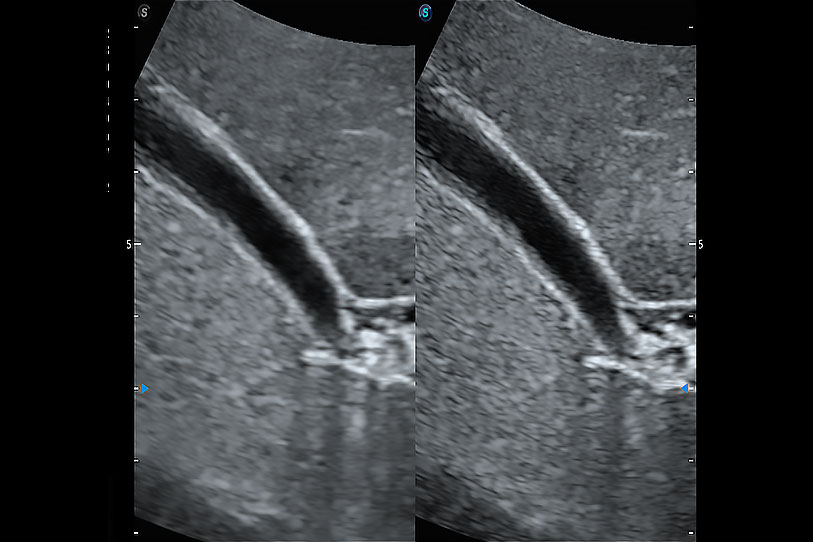

增强穿刺针在动物解剖结构中的位置,提高穿刺介入的安全性和准确性。

为精细结构及组织边缘提供高清晰度的图像和更大的成像视野。帮助减轻医生的用眼疲劳,快速精准获得测量的数据。